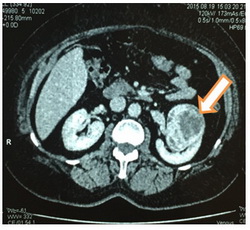

При МСКТ: в верхнем и среднем сегментах левой почки по передне-латеральной поверхности определяется мягкотканное образование неправильной формы неоднородной структуры размерами 6,9х5,8х6,8см.